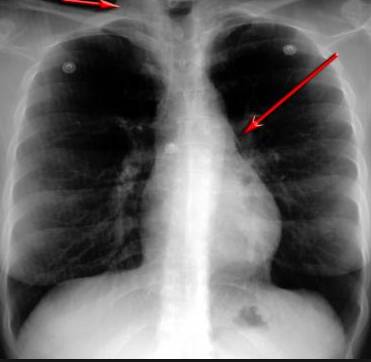

并且,因?yàn)楹粑到y(tǒng)結(jié)構(gòu)復(fù)雜,在體檢時(shí)醫(yī)生很難通過(guò)一種檢測(cè)手段,判定早期患者的病情。

使用這臺(tái)掃描儀,將直接把器官變成3D圖形!細(xì)微的毛細(xì)血管,幾毫米大的肺泡和支氣管,都將能看的一清二楚!

你的每一個(gè)氣泡,每一段支氣管,哪兒有病變都清清楚楚的將展示在醫(yī)生面前!

也就是說(shuō)在一切都還沒(méi)開(kāi)始惡化前,把這些有問(wèn)題的器官組織都暴露的一清二楚:

沒(méi)有這項(xiàng)新技術(shù),醫(yī)生在做體檢的時(shí)候,很難通過(guò)一種測(cè)試斷定一個(gè)人是否有呼吸系統(tǒng)疾病。

可是現(xiàn)在他們不但能看到整個(gè)肺部的3維結(jié)構(gòu)圖。還能看到空氣進(jìn)入人體后的所有微小變動(dòng)!